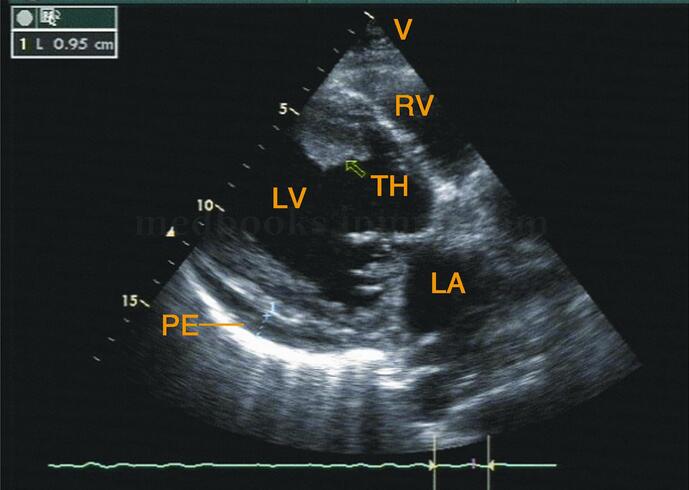

(3)左室心尖部附壁血栓形成,随室壁运动轻度移动。血栓回声水平根据形成时间不同、机化程度不同而呈略低或略高回声,形状不规则(图2‐1‐185)。

图2‐1‐185 左室长轴切面:室间隔靠近心尖部见一略强回声光团,中心回声略低;左室后壁后可见少量心包积液。TH:血栓